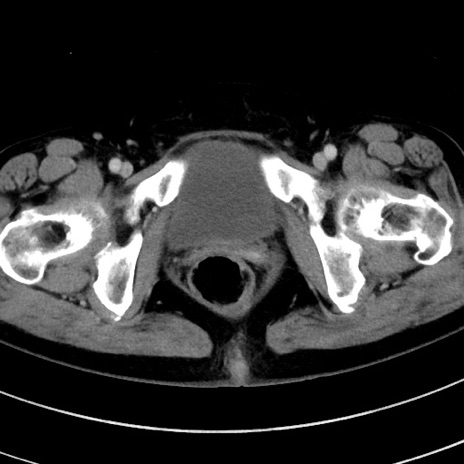

症例9(横断像)

【症例】 60歳代女性

【主訴】むかつき、みぞおちの痛み

【現病歴】3日前よりむかつきがあり、食事がとれない。

【既往歴】糖尿病

【身体所見】発熱なし、心窩部圧痛軽度あるも、腹膜刺激症状なし。

【データ】WBC 7400、CRP 1.92